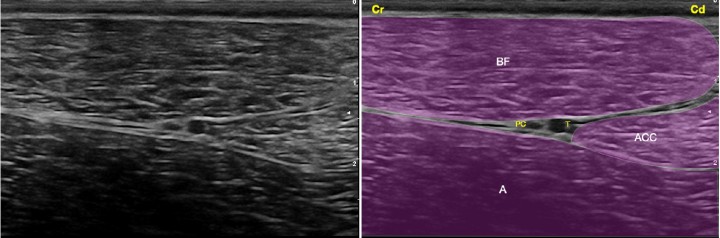

<p>Imagen ecográfica del nervio ciático a nivel del fémur medio. Músculo bíceps femoral (BF), músculo aductor (A), músculo aductor crural caudal (ACC), nervio ciático integrado por sus dos componentes: nervio peroneo común (PC) y nervio tibial (T). Cr: Craneal, Cd: Caudal.</p>

Figura 5

Imagen ecográfica del nervio ciático a nivel del fémur medio. Músculo bíceps femoral (BF), músculo aductor (A), músculo aductor crural caudal (ACC), nervio ciático integrado por sus dos componentes: nervio peroneo común (PC) y nervio tibial (T). Cr: Craneal, Cd: Caudal.

Bloqueo del nervio ciático con abordaje en el fémur medio

Se basa en el bloqueo del ciático una vez ha sobrepasado el trocánter mayor del fémur y la tuberosidad isquiática. Existen diferentes puntos para abordar el nervio que han sido descritos por varios autores. Esto se debe a que la ventana acústica que permite la ecolocalización del ciático en la cara lateral del muslo es grande. Para realizar la técnica se debe preparar adecuadamente la piel. Se utiliza un transductor de alta frecuencia (9-15 MHz) y se coloca ligeramente distal a la línea que une el trocánter mayor y la tuberosidad isquiática. El ciático se puede recorrer de proximal a distal. En su corte transversal se observa como una estructura hiperecogénica que contiene en su interior dos discos hipoecogénicos que se corresponden con los nervios peroneo común (craneal) y tibial (caudal). En su corte longitudinal el ciático se observa como una doble banda hiperecogénica que contiene en su interior una banda hipoecogénica. El abordaje de este se realiza con la aguja en plano, en su corte transversal en el punto donde el ciático se visualice adecuadamente[ Portela DA, Verdier N, Otero PE: Regional anesthetic techniques for the pelvic limb and abdominal wall in small animals: A review of the literature and technique description. Vet J 2018; 238: 27-40. [PubMed] , Campoy L, Bezuidenhout AJ, Gleed RD et al: Ultrasound-guided approach for axillary brachial plexus, femoral nerve, and sciatic nerve blocks in dogs. Vet Anaesth Analg 2010; 37: 144-153. [PubMed] , Echeverry DF, Gil F, Laredo F et al: Ultrasound-guided block of the sciatic and femoral nerves in dogs: A descriptive study. Vet J 2010; 186: 210-215. [PubMed] ] (Fig. 10). En raras ocasiones resulta necesario el empleo del neuroestimulador en este bloqueo, pero en caso necesario se procederá de la forma descrita anteriormente, observando la dorsiflexión o extensión del tarso. En este punto se administran de 0,05 a 0,1 ml/kg del AL seleccionado intentando rodear el nervio en su totalidad. Se recomienda el empleo de bupivacaína 0,5% o ropivacaína 0,5% con 0,5-1 µg/ml de dexmedetomidina.